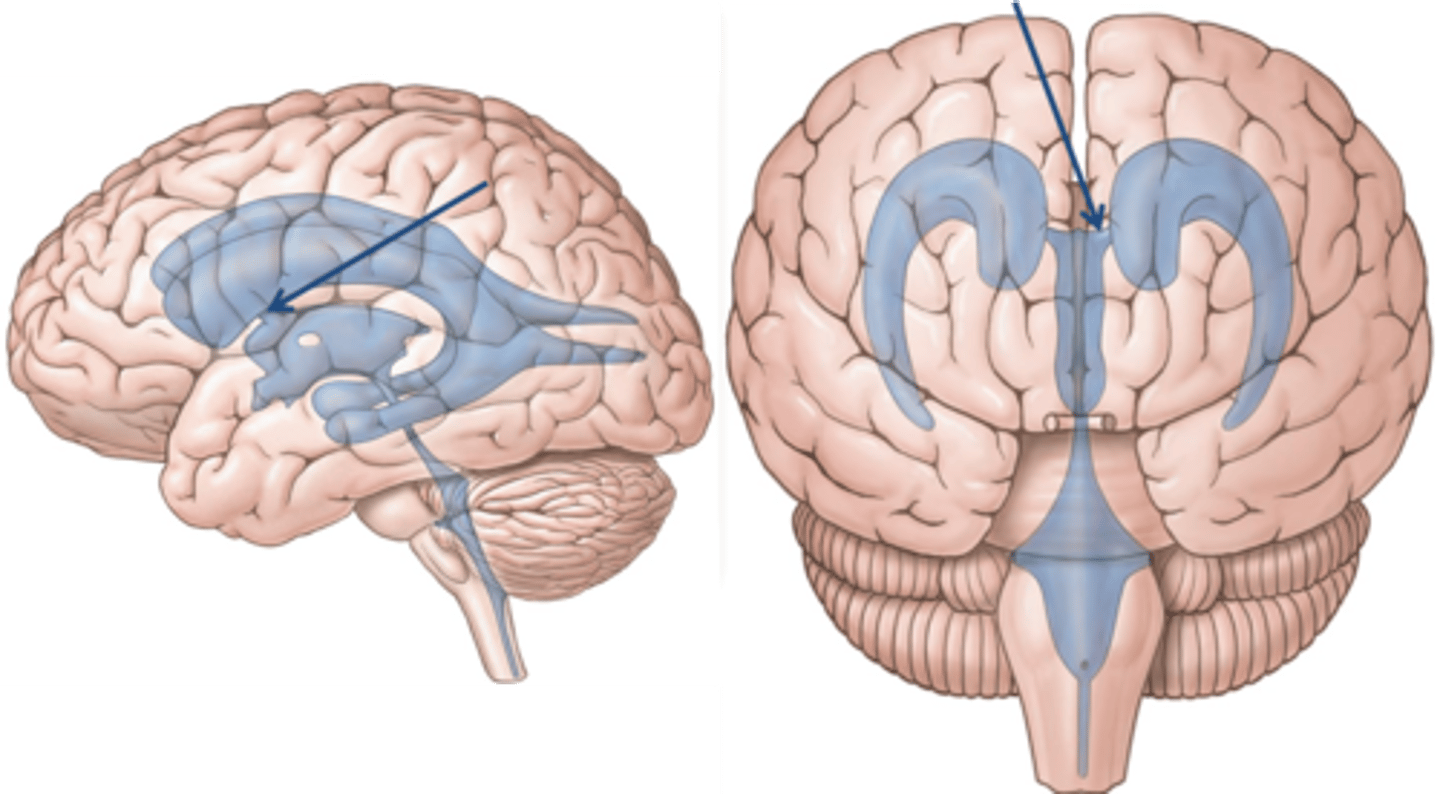

right and left lateral ventricles

third ventricle

fourth ventricle

cerebral aqueduct (mesencephalic aqueduct)

interventricular foramen